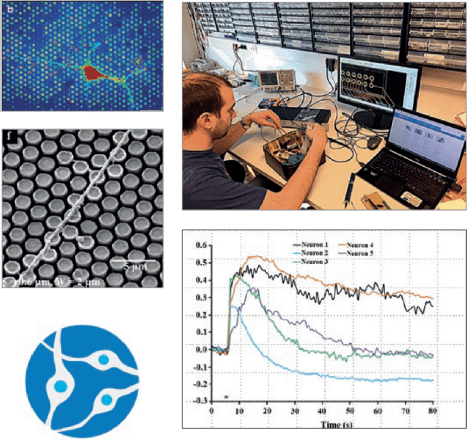

- Interaction between light and biological matter

- Biosensorics with superior detection is based on metallic nanoclusters stabilized by biomolecules (new class of non-linear fluorophores) which allow deep tissue penetration and direct imaging of living cells for early medical diagnostics

- Experimental part: Dr. Rodolphe Antoine and Dr. Philippe Dugourd (Université Claude Bernard Lyon 1, CNRS, Lyon, France)